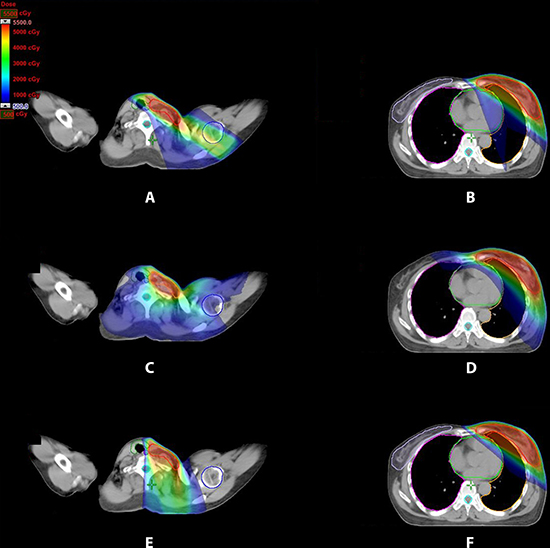

Treatment plans generated using the three techniques tangential-IMRT, VMAT and FJT-IMRT for 16 left-sided breast cancer patients previously treated with radiotherapy after lumpectomy. The dose distributions in the periclavicular and the breast/IMN regions for one representative patient were illustrated in Figure 1. VMAT plan showed low dose irradiation for all OARs, including the contralateral breast and the contralateral lung. Compared with tangential-IMRT and VMAT, FJT-IMRT had avoided irradiating part of the thyroid gland and spared the entire humeral head.

Figure 1: Dose distribution for three treatment plans for periclavicular node, left breast and IMN region for one representative patient. (A, B) tangential-IMRT (C, D) VMAT (E, F) FJT-IMRT.